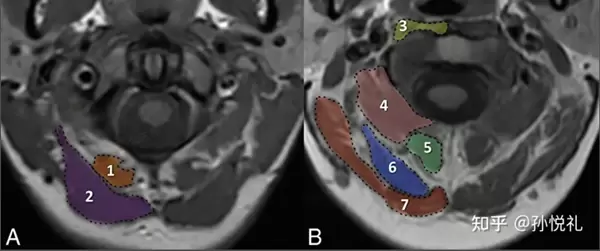

例如,知乎答主孙悦礼是上海中医药大学附属龙华医院的骨科医师,在去年知乎好物100活动中,曾用500万的核磁共振机器和150万的材料力学测试仪,测试了8中市面上不同材料的颈椎枕。

知乎答主孙悦礼在颈椎核磁共振影像中观察肩颈肌肉形态

在2022“知乎好物100”中孙悦礼的好物提案,是帮大家找到一款放松效果明显的颈椎按摩仪。孙悦礼挑选了6名硕士博士研究生作为评测的受试者,在使用每个颈椎按摩仪后,从重量、活动度、力度、精度、外观五个方面进行打分;不仅如此,孙悦礼还通过柔性传感薄膜(电子皮肤)和医院常用的超声扫描仪,客观动态测量按摩仪从人体体表到深层的外力施加作用,再给按摩仪进行综合评分;最后,根据每个产品的价格和实际的分值,来定义不同按摩仪的性价比。